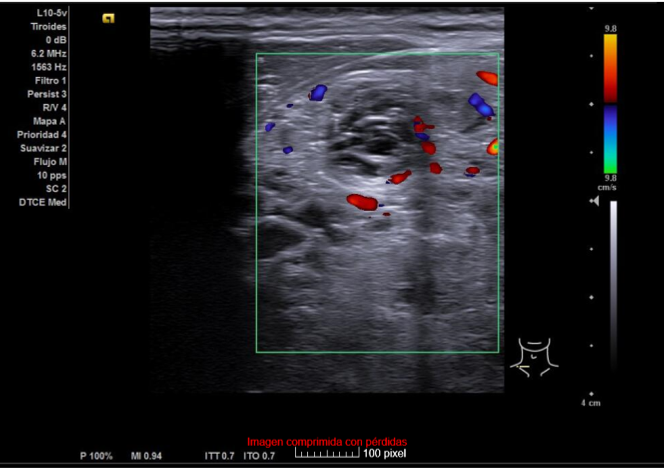

Hallazgos ecográficos

Ecografía clínica de tiroides: Glándula tiroides muy aumentada de tamaño. Istmo irregular de 20 mm. Lóbulos tiroideos desestructurados, aumentados de tamaño (siendo mayor el derecho) y presencia de múltiples nódulos, algunos anecogénicos y otros de estructura espongiforme. No se aprecia aumento de vascularización con modo Doppler que descarta situación de tormenta tiroidea.